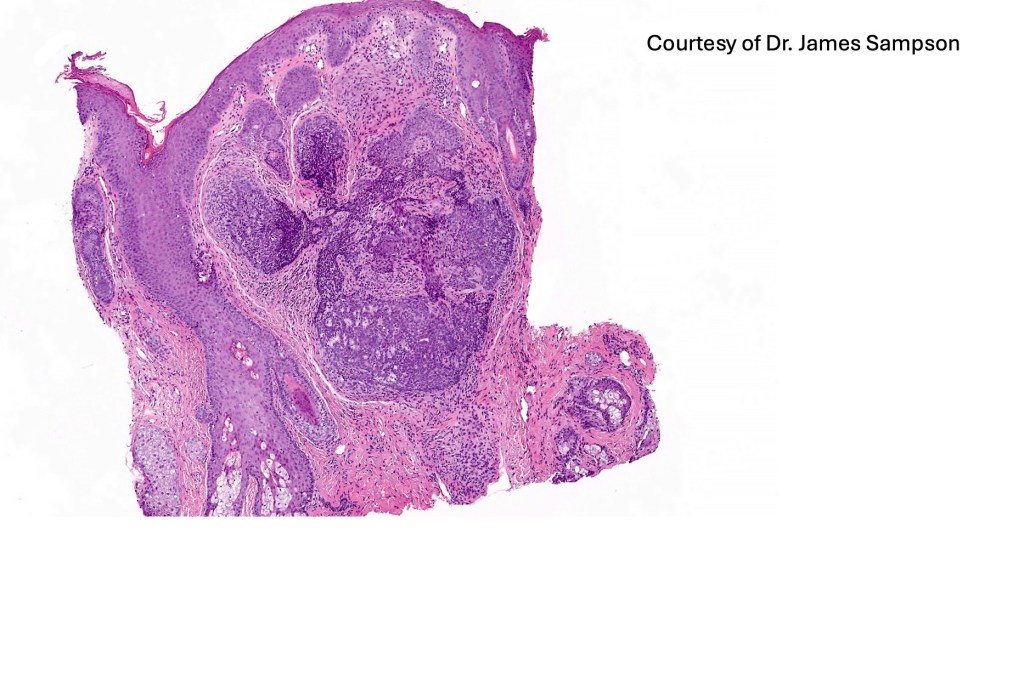

Histological features

•The classical appearance consists of keratocysts & lobules of basaloid cells

•Some tumors are devoid of keratocysts

•Variable continuity with the epidermis

•Basaloid lobules show peripheral palisading

•Retraction artifact and mucin deposition as seen in BCC are not present

•Mitoses & apoptosis may be present

•Perifollicular mesenchyme is always conspicuous and sometimes densely aggregated are seen indenting the baslaloid lobules (papillary mesenchymal bodies)

•Narrow epithelial strands arising from the basaloid lobules are often present

•Amyloid, foreign body granuloma formation to free keratin & calcification are variable features

Trichoepithelioma should be distinguished from trichoblastoma since the latter is very rarely syndromic. Trichoepithelioma is largely a dermal tumor whereas trichoblastoma often extends from the dermis into subcutaneous fat or deeper in very large examples. Papillary mesenchymal bodies are much better formed and generally more obvious in trichoepithelioma. Trichoepithelioma must also be distinguished from basal cell carcinoma. Retraction artifact & stromal mucin are features of basal cell carcinoma and not trichoepithelioma. Papillary mesenchymal bodies are not seen in basal cell carcinoma.